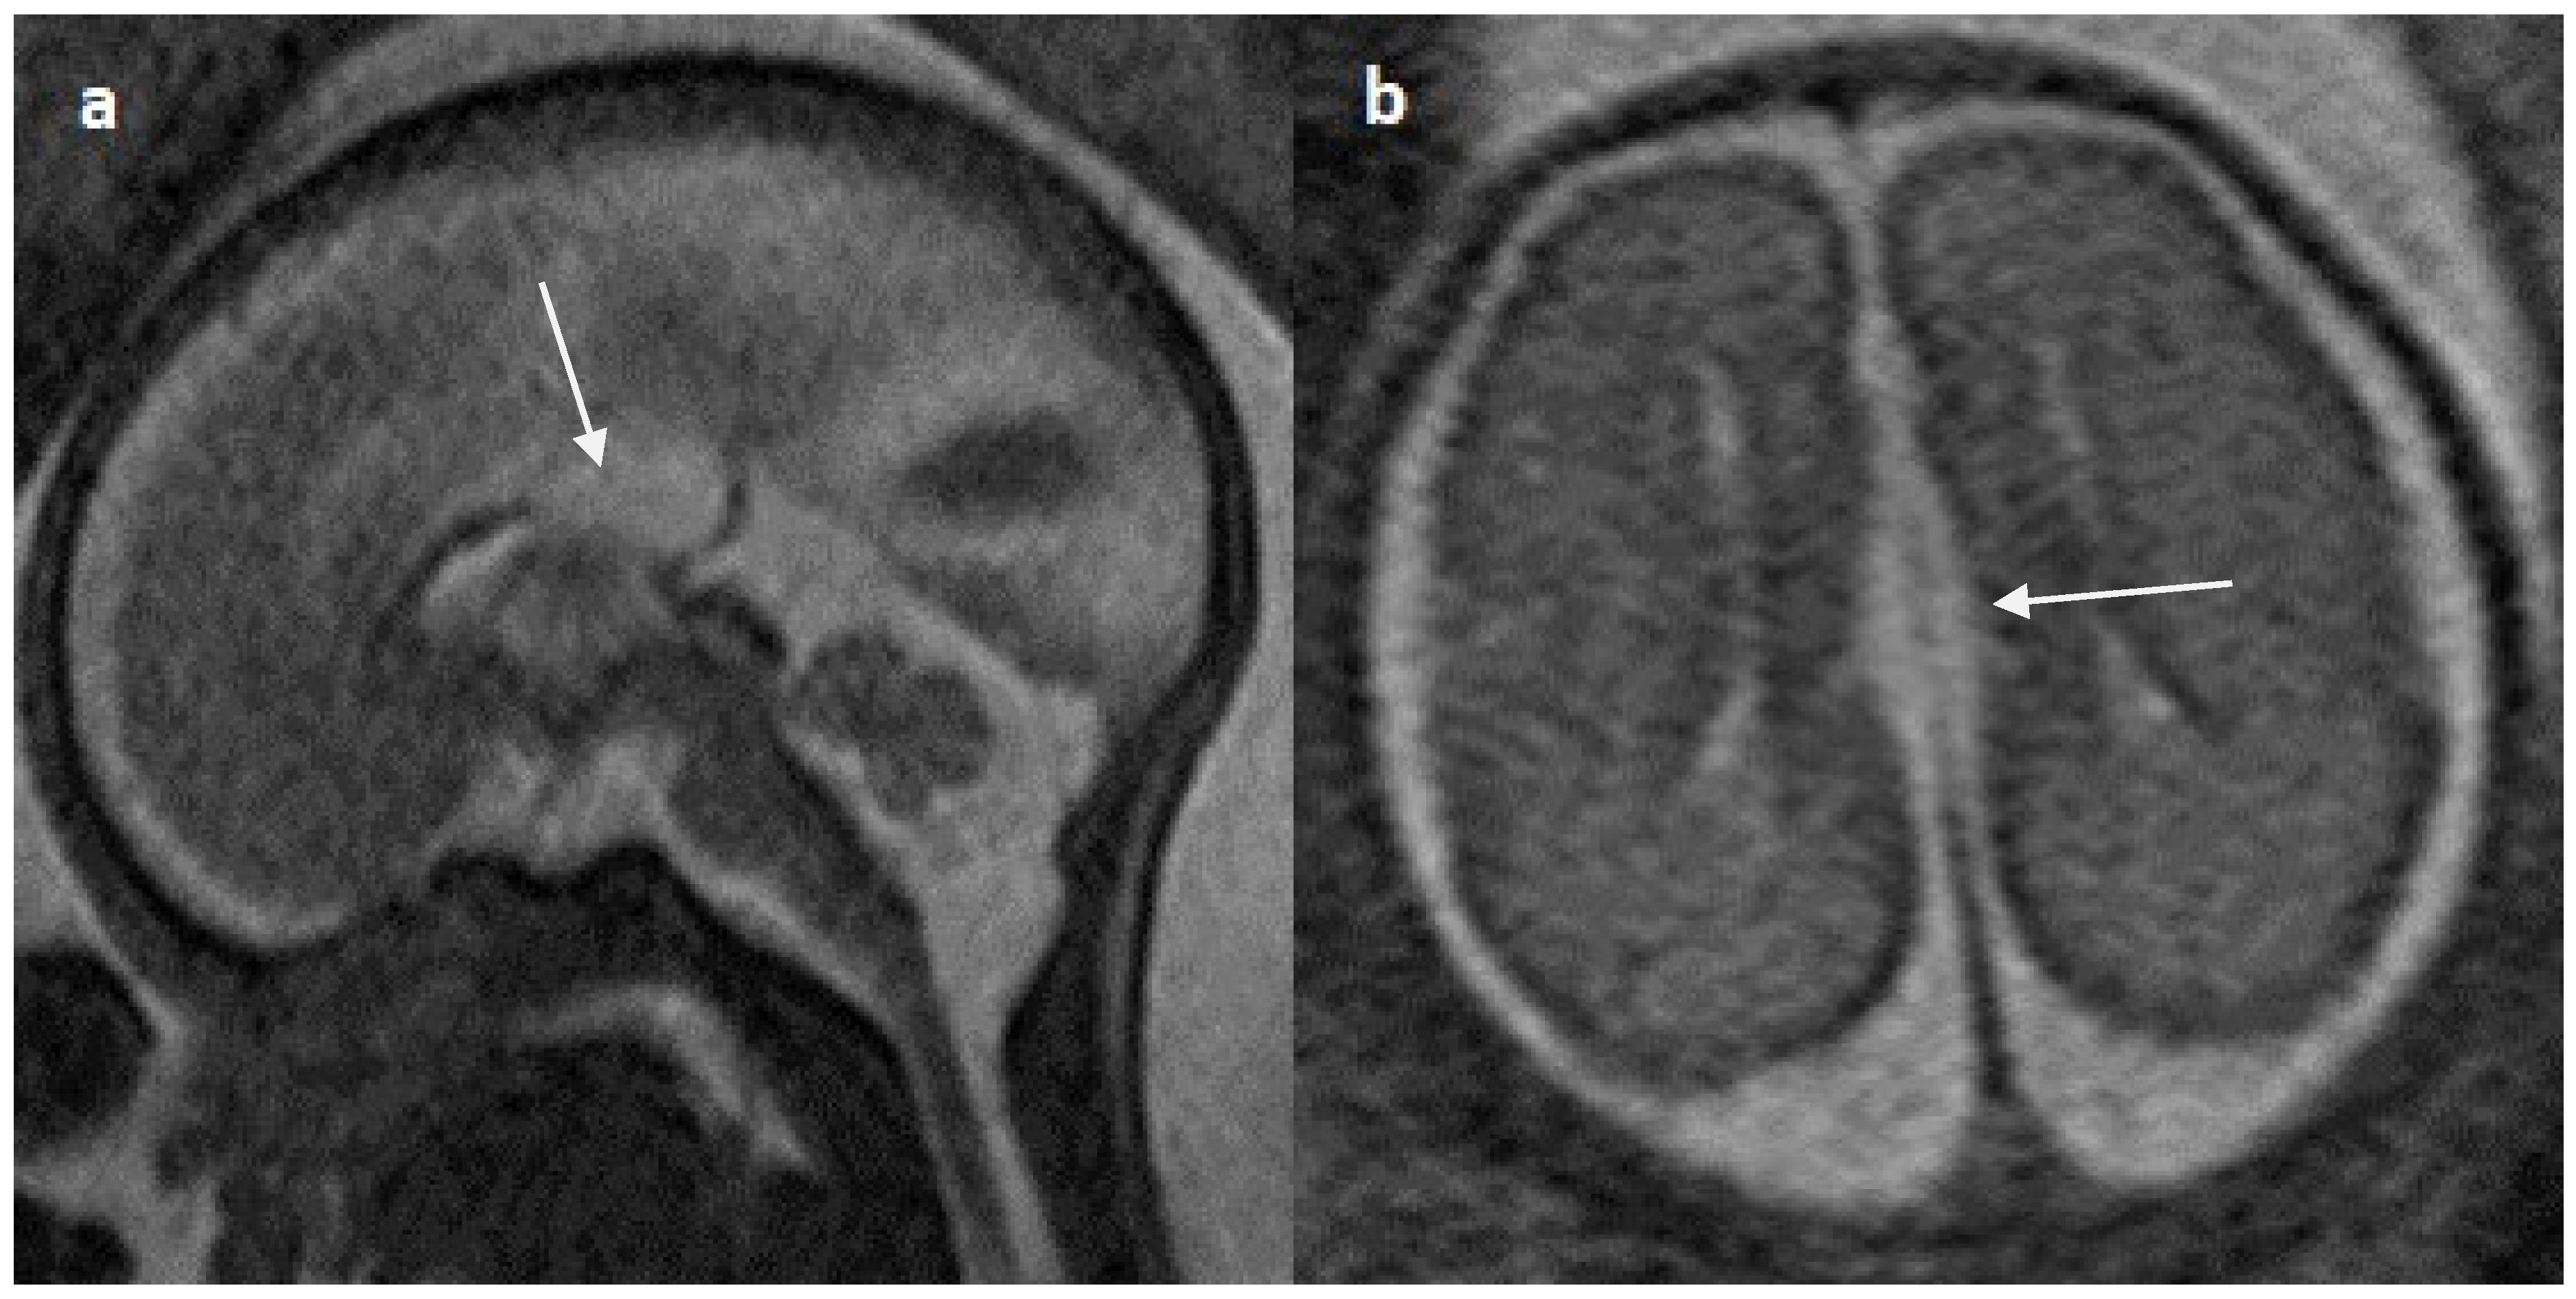

Figure 6.

Fetal MRI images of a 29 gestational weeks aged fetus in a case of hypoplasia with dysplasia of the corpus callosum. (a) A T2-weighted sequence in axial plane showing severe dilatation of the lateral ventricles, particularly at the body and atria, with thinning of the brain parenchyma in the posterior parieto-occipital region, and an associated absent cavum septum pellucidum was noted (white arrow). (b) A T2-weighted sequence in midsagittal plane shows thin anterior corpus callosum with dysplasia. Additionally, hypoplasia of the inferior vermis is noted (white arrow).